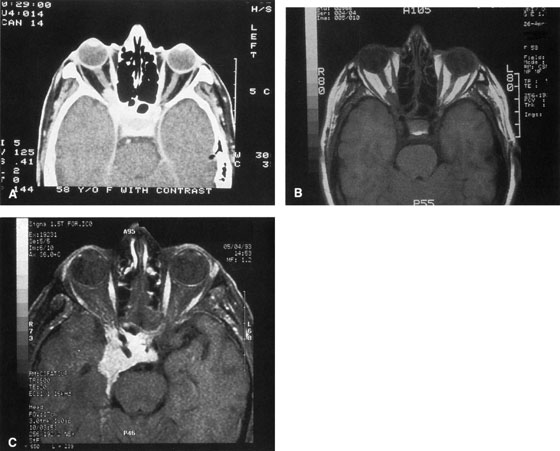

Magnetic resonance imaging is useful in selected cases, especially when evaluating the orbital cranial junction. Significant bony artifact and a lack of orbital fat in the orbital apex make CT scan resolution of the orbital apex structures poor. Because cortical bone has low signal on MRI, there is no bone artifact when viewing the orbital apex on MRI. The lack of intervening fat in the apex to provide contrast is overcome on MRI because contrast is provided by the individual nuclear characteristics of each tissue so that the orbital apex structures are visualized well. Consequently, conditions that affect the optic nerve and chiasm, such as optic nerve meningioma and glioma, generally are evaluated with MRI rather than CT scan (Fig. 2).

Fig. 2. A. Axial orbital CT scan of right optic nerve meningioma. Note lack of detail in orbital apex. B. Axial orbital MR image, same patient. Note increased detail in orbital apex owing to lack of bone artifact. C. MRI with gadolinium contrast. Note extension into brain not easily appreciated with CT scanning or MRI without contrast.